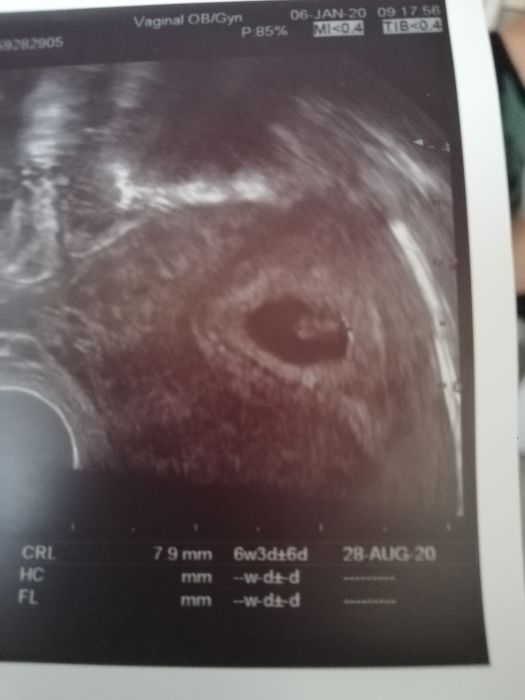

On se prave dava proto ten druhy termin, ktery se koriguje dle utz. Protoze u MS se kalkuluje s tim, ze k otehotneni doslo prave v polovine cyklu. Coz nemusi byt vzdy. Ja u prvniho mela prvni termin 21.7. ale se stoprocentni jistotou jsem vedela, ze jsem otehotnela asi az o 10 dni dele nez byla ovulace, coz potvrdil i utz. A tim padem jsem mela druhy termin 1.8. a syn se narodil 28.7. Ja mam fotecku z 19.12.Dalsich snad pristi tyden ?

Ahojky, tak jsem byla dneska na ultrazvuku a prý je plod menší, takže mi to zatím vychází na 6+3tt.Na screening jdu 4.unora tak uvidíme vo řeknou tam